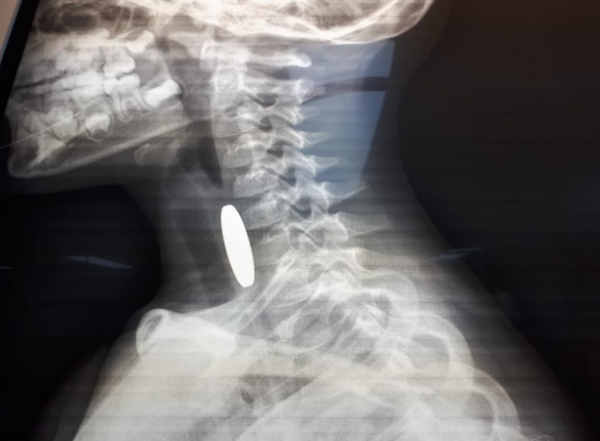

Ammon News - A patrol from the Madaba Police Department rescued a three-and-a-half-year-old boy who was choking on a coin in the Dhiban district.

The boy’s father told Amen FM that upon realizing his son was struggling to breathe, he rushed him to Princess Salma Government Hospital. A nearby police patrol responded to his call for help. After being informed that the boy had swallowed a coin, the officers promptly and professionally provided first aid.